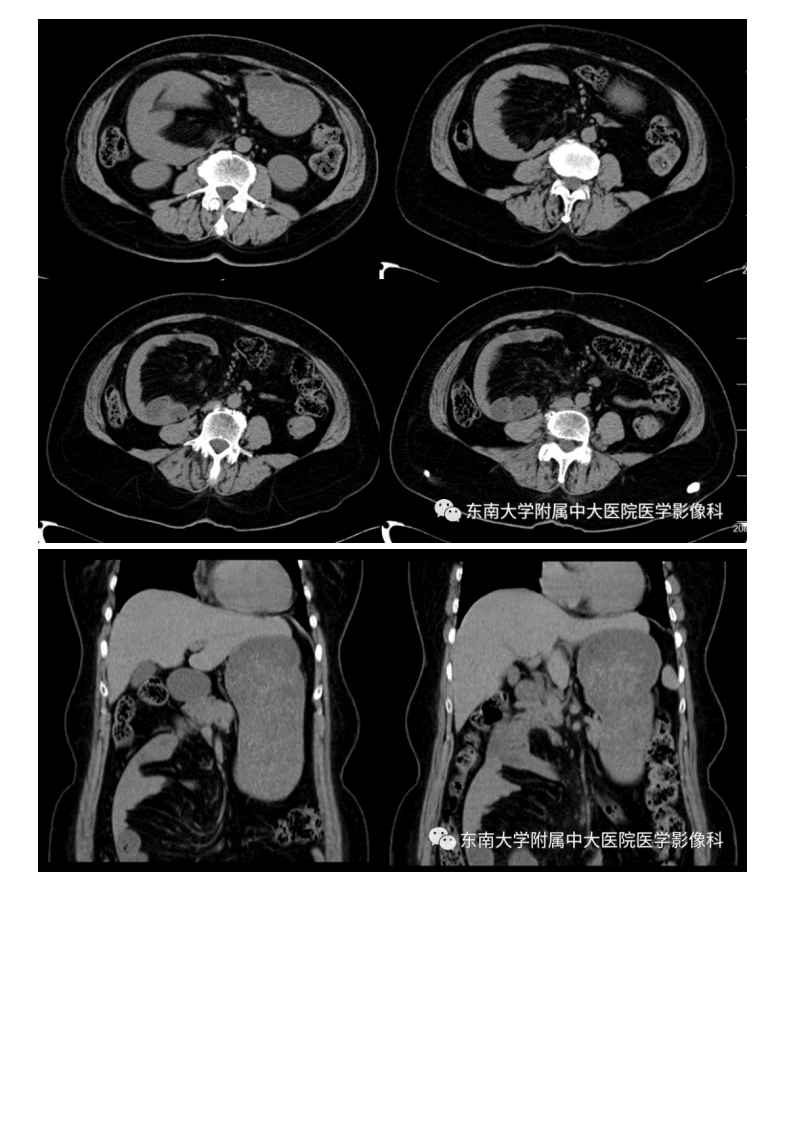

20201014_2【晨读结果公布】2020.10.14消化系统疾病——腹内疝.pdf